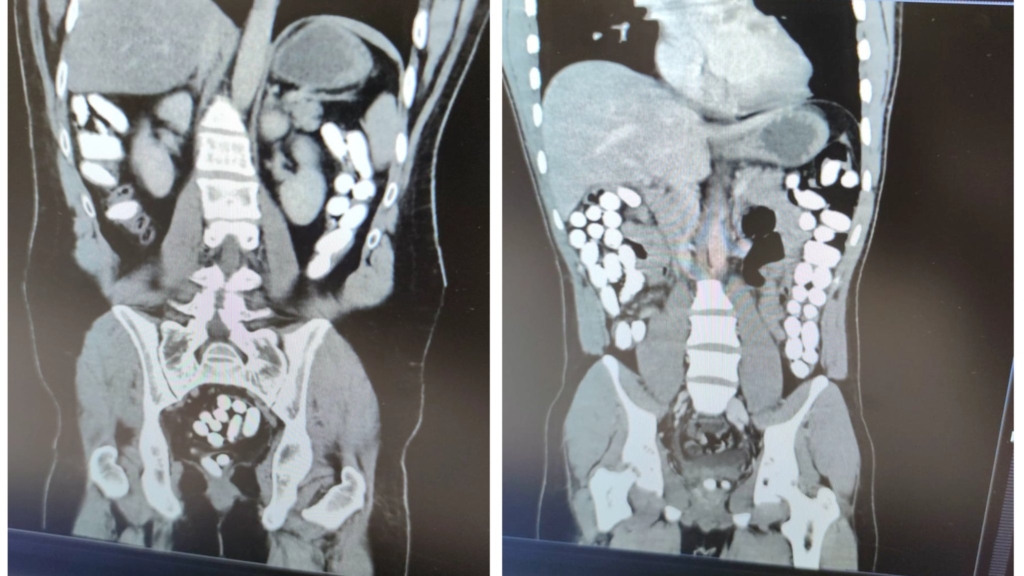

Hastaneye götürülerek muayene ve tomografi çekimleri yapılan şüphelilerin mide ve bağırsaklarında çok sayıda yabancı cisim bulunduğu tespit edildi. Yapılan tıbbi müdahaleyle E.P. ve A.G’nin midesinden 242 kapsül halinde çıkarılan 1 kilo 919 gram afyon sakızına el konuldu.